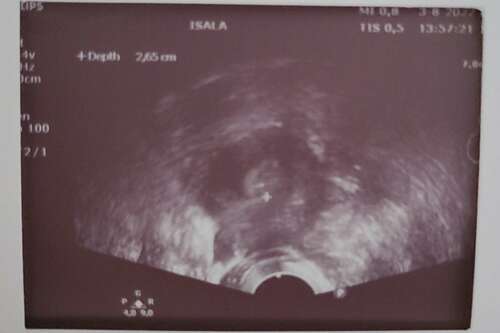

Mini is weer geplaatst. Hij zit bij het +🍀

Kleine frummel. Ga voor je duimen!